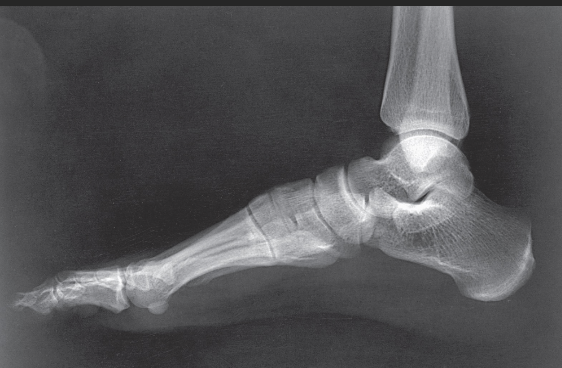

Name this projection.

Lateral ankle

What type of projection is it?

Mediolateral

Which side is the patient turned toward?

Affected side

Where does the CR enter?

Perpendicular to the ankle joint, entering at the medial malleolus

How do you evaluate for a true lateral?

The tibiotalar joint will be well visualized, and the fibula will be over the posterior half of the tibia

How much of the distal tibia and fibula must be included?

1/3

Which joint is well visualized?

Tibiotalar